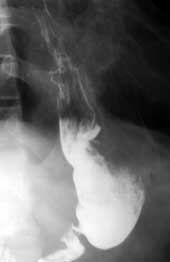

Патологические процессы, локализующиеся в верхних отделах желудка, в основном опухолевого генеза, завершаются выполнением проксимальной резекции желудка с формированием гастроэнтеростомы. Анастомоз формируется с оставшейся частью антрального отдела желудка или даже с препилорической зоной (Рис. 4). Культя желудка имеет форму трубки с перетяжкой в области анастомоза, то есть напоминает так называемые песочные часы, имеет относительно ровные и четкие контуры. Обычно не наблюдается существенных изменений тонуса и перистальтических сокращений культи желудка. Достаточно разноречивы сведения об эвакуаторной функции. Чаще наблюдается обычный ритм эвакуаторного процесса, имеющий порционноритмический характер и связанный с функционированием пилорического жома. Замедляющим или ускоряющим фактором эвакуации содержимого является возбуждающее или тормозное влияние на канал привратника вегетативной нервной системы, подвергшийся воздействию при хирургическом вмешательстве. У подавляющего числа больных после гастроэзофагостомии наблюдается желудочнопищеводный рефлюкс. Большинство авторов считают, что никакие технические мероприятия не позволяют восстановить клапанный механизм функционирования пищеводножелудочного перехода, лишь обращается внимание на методики позволяющие избежать в последующем сужения соустья.

Рис. 4. Культя желудка после субтотальной проксималъной резекции.